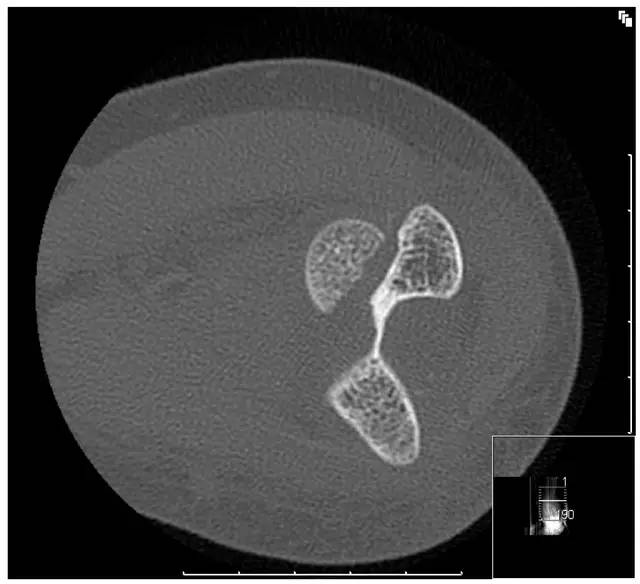

Hahn-steinthal 骨折 CT 片(来源:Hahn-Steinthal fracture: a case report.BioMed central Cases Journal20081:239)